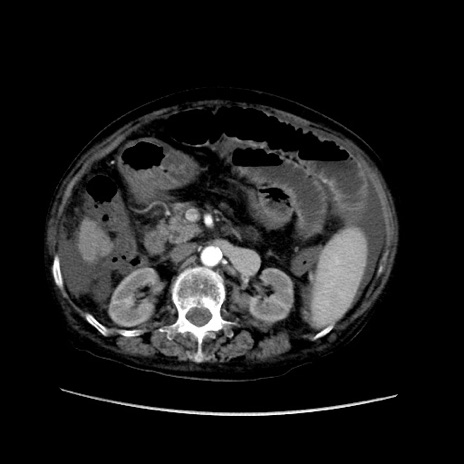

症例31(横断像)

【症例】80歳代 女性

【主訴】腹部膨満感

【現病歴】他院にて肝硬変にてフォロー中。1週間前から便秘、腹部膨満感、臍部腫瘤あり受診となる。

【既往歴】肝硬変

【身体所見】腹部膨隆あり、皮膚変化なし、疼痛なし。

【データ】WBC 4600、CRP 0.25